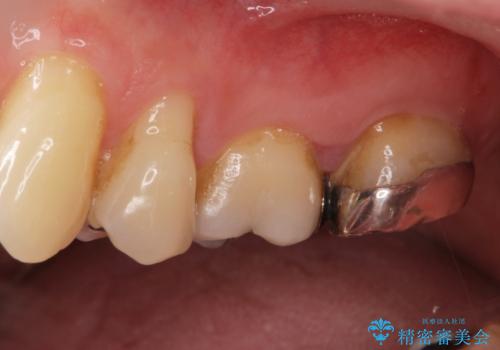

被せ物、古い材料を徹底的に除去し、ラバーダム防湿にて無菌的処置を行い、セラミックの被せ物で治療を行いました。

治療が終了してからも定期的にレントゲンをとり経過観察を行いました。

病巣は現在縮小しておりまた白い被せ物が入り患者様に満足してもらえました。